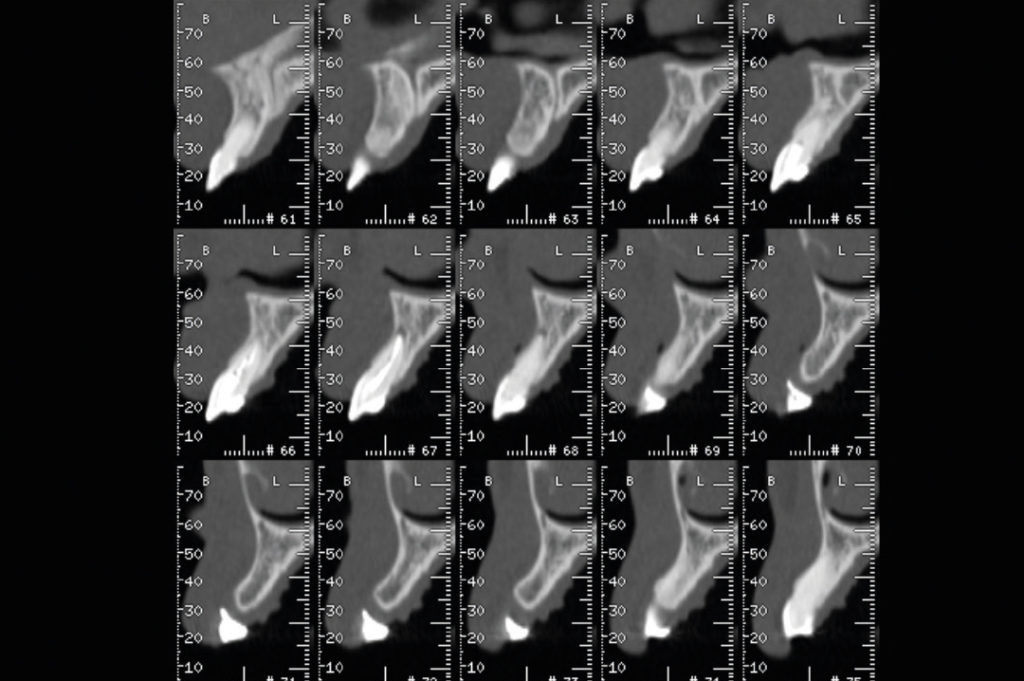

Vista axial con cortes transversales en DVT

Imágenes DVT